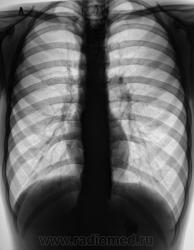

Пациент направлен на рентгенологическое исследование ЖКТр из военкомата с диагнозом - "Хронический гастрит". Пациенту неоднократно проводилась ФГДС. В течение последник 6 лет наблюдается и обследуется в области по поводу хронического гастрита и невроза пищевода. Произведено стандартное исследование.

При обзоре газа в газовом пузыре не было.

Направлен "от военкомата" - 17 лет. Мальчик худоват. На мой вопрос по поводу жалоб ответ был интересный - "после приема любой пищи - срыгиваю". Именно "срыгивает". Ест малыми порциями. Невроз и гастрит приклеены, как диагноз, в течение 6 лет.

Ахалазия пищевода. Почему ослабленный лег. рисунок в верхних поясах легочных полей.